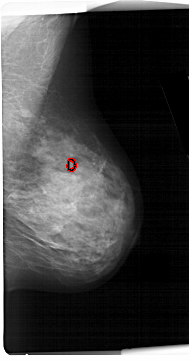

A_1133_1.RIGHT_CC

RIGHT_CC LINES 6361 PIXELS_PER_LINE 3706 BITS_PER_PIXEL 12 RESOLUTION 43.5 OVERLAY

FILE: A_1133_1.RIGHT_CC.OVERLAY

TOTAL_ABNORMALITIES 1

ABNORMALITY 1

LESION_TYPE CALCIFICATION TYPE PLEOMORPHIC DISTRIBUTION CLUSTERED

ASSESSMENT 4

SUBTLETY 1

PATHOLOGY MALIGNANT

TOTAL_OUTLINES 1

BOUNDARY